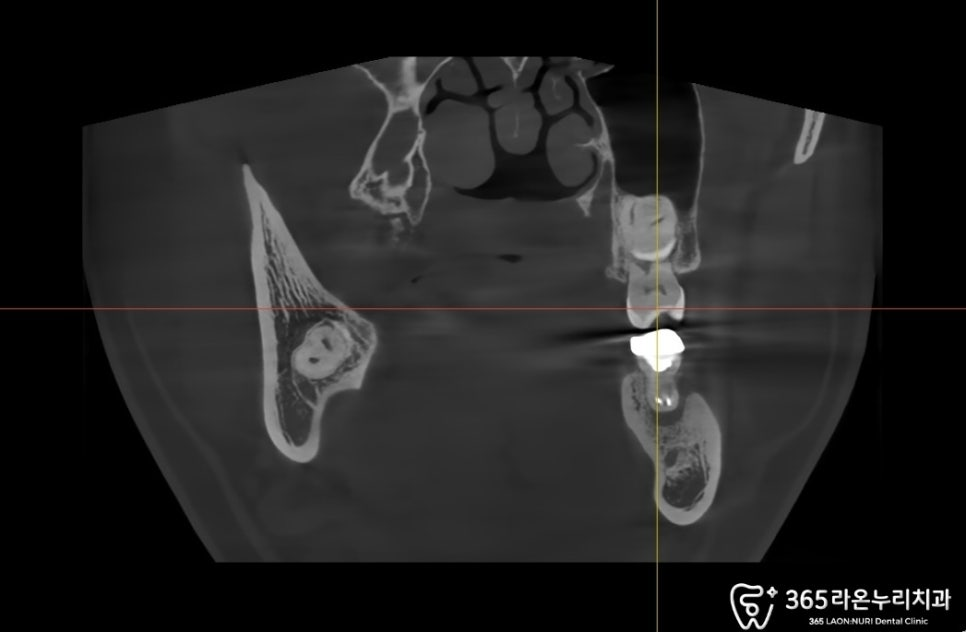

▮ 임플란트 과정

2024.12.21

먼저 시술 전 CT를 찍어 식립 각도와

방향 깊이등을 설정해줍니다.

보통 골 이식이 시행되며, 이후 식립하게 됩니다.

먼저 뼈이식을 진행 후

픽스처를 식립하는데요.